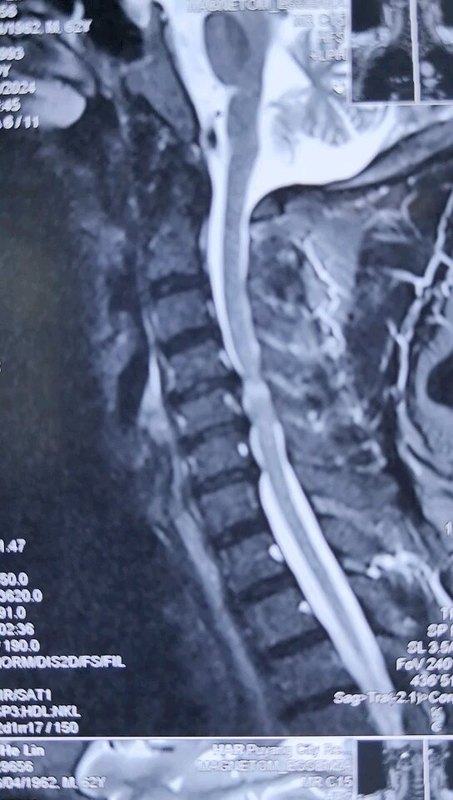

不少患者查出頸椎病后,發(fā)現(xiàn)不是頸椎受壓就是脊髓受壓,這兩種情況有什么不同呢?哪一種更嚴(yán)重呢?如果既壓迫到神經(jīng),又壓迫到脊髓,又該怎么辦呢?頸椎病壓到神經(jīng)和脊髓,有什么不同?事實上,這個問題是在對比神經(jīng)根型頸椎病和脊髓型頸椎病。頸椎病由于頸椎退化等各種原因?qū)е轮車纳窠?jīng)根、脊髓、血管等組織受壓,導(dǎo)致出現(xiàn)一系列癥狀。根據(jù)受壓組織不同,頸椎病又分為許多類型,其中最常見的就是神經(jīng)根型頸椎病,最嚴(yán)重的就是脊髓型頸椎病。顧名思義,神經(jīng)根型頸椎病常由于頸椎間盤突出等原因?qū)е律窠?jīng)根受壓,患者常會出現(xiàn)上肢的放射性疼痛、麻木、無力等癥狀;而脊髓型頸椎病壓迫到脊髓,患者除了上肢癥狀外,還會出現(xiàn)下肢的走路踩棉花感、走路不穩(wěn)等情況。這兩種類型的頸椎病治療方案也略有不同,神經(jīng)根型頸椎病多數(shù)情況下保守治療就可以了,只有患者的病情嚴(yán)重,保守治療無效,嚴(yán)重影響生活了才會考慮手術(shù)干預(yù)。但脊髓型頸椎病是一旦確診就需要盡快手術(shù)的,保守治療效果不好,而且脊髓長時間受壓,可能會導(dǎo)致一些不可逆的功能障礙。既壓到神經(jīng),又壓到脊髓,這種頸椎病要怎么辦?最近,宣武醫(yī)院王作偉主任接診了一位44歲的女性頸椎病患者。這位患者出現(xiàn)脖子疼痛、僵硬已經(jīng)有3年了,難受的時候會做熱敷、針灸,但在2個月前,她的右側(cè)上肢出現(xiàn)了放射性疼痛,麻木乏力,偶爾時不時還會出現(xiàn)走路腳底有踩棉感,這讓她非常難受,去了當(dāng)?shù)蒯t(yī)院檢查出頸椎病?;颊邽榱诉M(jìn)一步治療,最后找到王主任。從她的片子、查體等檢查結(jié)果上看,她的頸椎生理曲度消失,甚至有點反弓,而且在頸4-7多個節(jié)段出現(xiàn)了椎間盤突出,突出不僅壓迫到了神經(jīng)根,同時也壓迫到了脊髓。這種情況該怎么辦?這樣的情況,王主任建議進(jìn)行手術(shù)治療。兩者都受到壓迫,尤其是她出現(xiàn)脊髓受壓,并出現(xiàn)下肢走路問題,這時保守治療已經(jīng)沒有太大效果,這種情況還是要盡快手術(shù)處理。術(shù)前影像學(xué)資料:在獲得患者和家屬的同意后,王主任為她成功進(jìn)行了手術(shù)治療。手術(shù)對突出的椎間盤進(jìn)行了切除,給神經(jīng)根和脊髓進(jìn)行了徹底減壓,并給頸椎進(jìn)行內(nèi)固定,重建了穩(wěn)定性。術(shù)后,患者的上肢疼痛立馬得到極大緩解,不到第3天,她就已經(jīng)可以戴著頸托獨自行走了,其余的麻木、乏力癥狀也在逐漸好轉(zhuǎn)。術(shù)后影像學(xué)資料:最后,不管您是神經(jīng)根受壓、脊髓受壓,還是兩個都受壓,出現(xiàn)類似上面這些癥狀時,都要及時去醫(yī)院檢查。若單純是神經(jīng)根型頸椎病,對生活影響不大,建議您先保守治療;若是壓到脊髓或兩個都壓到了,就要考慮盡快手術(shù)干預(yù)了。